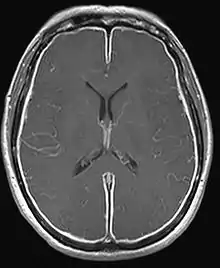

| T1W MRI of the brain demonstrating leptomeningeal enhancement consistent with meningitis | |